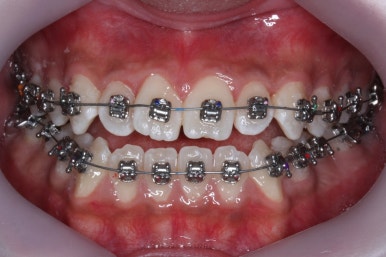

부산주걱턱교정 키다리아저씨치과에서 장치를 부착하였습니다.

이번에 사용된 장치는 자가결찰 메탈이며 가장 부피도 작고 튼튼하고 여러 장점이 있습니다.

점점 수술전 교정이 진행되는 모습입니다.

각각의 위턱과 아래턱뼈 제위치에 맞게 윗니는 뒤로, 아랫니는 앞으로 내어주게 됩니다. 수술직전까지는 어떻게 보면 교합은 점점 나빠진다고 볼 수 있씁니다.

이 과정에서 힘들어 하시는 분들이 많으신데요. 점점 교합이 서로 멀어질수록 수술은 예쁘게 잘 된답니다.